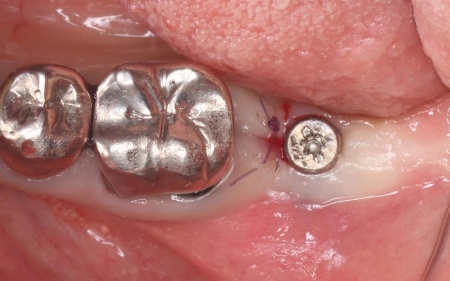

治療中

インプラント体と骨の結合を確認しました。